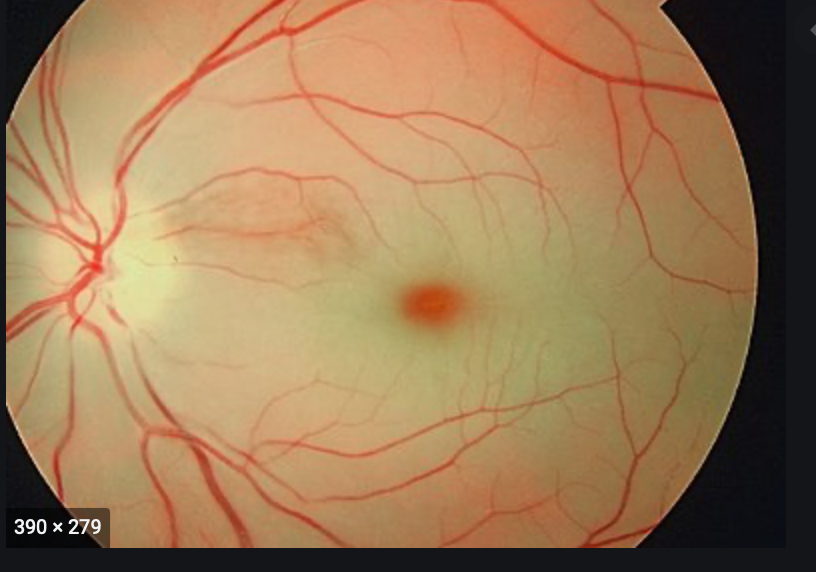

Central Artery Occlusion

Pale with cherry red spot